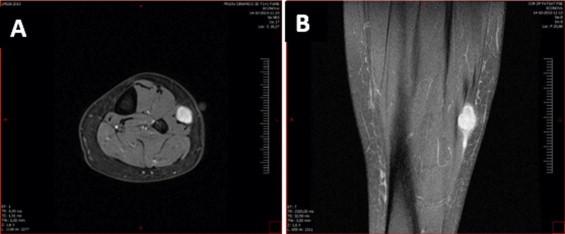

A 52-year-old Caucasian female arrived to our Orthopedics Department complaining of pain and numbness of the lateral aspect of her left leg. These symptoms were present for a year and were more evident at the end of the day, or after a long time in the orthostatic position. No evidence of other medical illnesses was found. There was no record of prior traumatic events related to that limb. Diagnosis of a benign peripheral nerve tumor was achieved and the patient was treated by surgical excision of the lesion.

一名52岁的白种女性来到我们骨科就诊,主诉左腿外侧疼痛和麻木。这些症状已出现一年,在一天结束时或长时间处于直立姿势后更为明显。未发现其他内科疾病的迹象。没有该肢体既往创伤事件的记录。诊断为良性周围神经肿瘤,患者接受了病变的手术切除治疗。